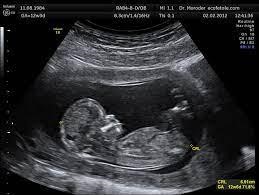

Los sistemas de imágenes médicas tienen limitaciones debidas a su tecnología, por lo cual, las imágenes obtenidas pueden aparecer borrosas o con ruido, o las estructuras anatómicas pueden mostrarse distorsionadas. Por ejemplo, si observamos la ecografía de un bebé en gestación, vamos a notar un ruido que se ve como puntos blancos y negros, y la anatomía del bebé no se aprecia claramente. Se requiere de un experto para interpretar la imagen.

examen ecografía fetal

Ecografía de un feto